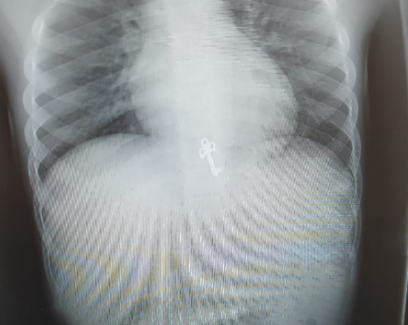

המפתח של יומן הכיתה שחיפשה הנערה מהמשפחה הירושלמית, נמצא לאחר צילום חזה בקיבה של בן המשפחה בן השבע.

המשפחה הגיעה למיון של יד שרה לאחר שעלה להם החשד שהאח בן השבע בלע את המפתח הדוקרני הקטן של היומן.

בצילום חזה, מצא רופא הילדים ד"ר חגי שטרן את המפתח הזעיר כשהוא בקיבתו של התינוק. היותו של המפתח משונן ודוקרני חייב פעילות פולשנית של הוצאת המפתח מחשש לסיכון ולקרע במעבר למעי, ובשל כך הועבר התינוק לחדר ניתוח בבית החולים.